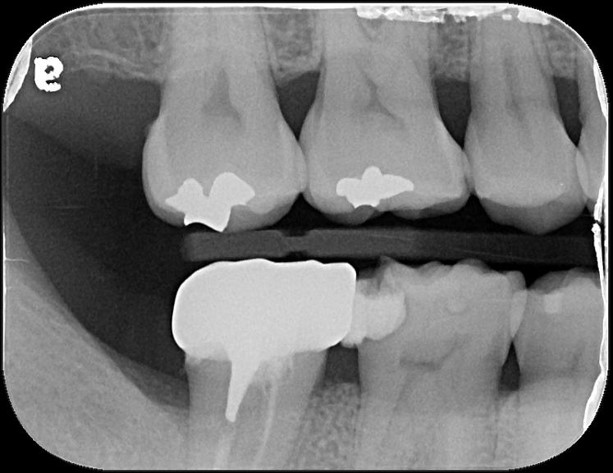

冠塊體體製備

當蛀牙破壞程度大